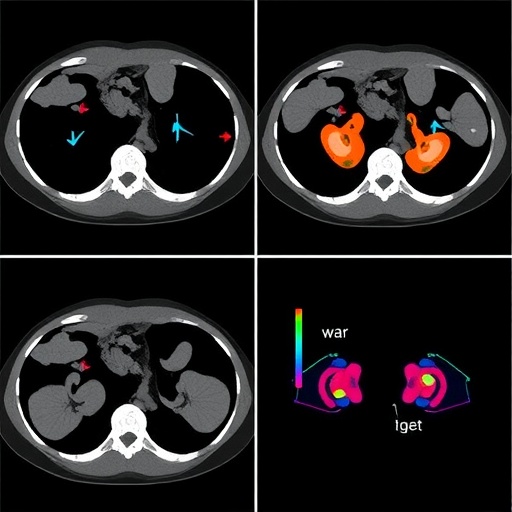

The model’s design incorporated hierarchical fusion strategies, effectively merging peri-tumor imaging histology with dual-view deep learning inputs, encompassing both clinical and radiomic features. This hierarchical integration enables the capture of nuanced spatial heterogeneity surrounding tumor regions, which is crucial for detecting subtle microinfiltrative patterns invisible to conventional imaging analyses. By harnessing imaging data at multiple scales and perspectives, the model leverages complementary information to refine its predictive capabilities.

Beyond statistical performance, interpretability was a pivotal focus for the researchers. Using Gradient-weighted Class Activation Mapping (Grad-CAM), the model’s attention regions were visualized, revealing substantial overlap (81%) with radiologist-annotated zones. This alignment not only instills trust in the algorithmic decision-making process but also facilitates clinician engagement by visually linking computational outputs with familiar diagnostic landmarks.